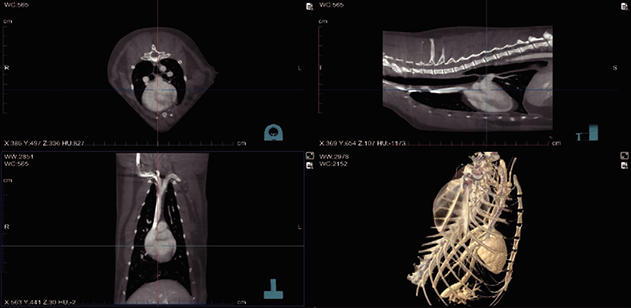

Imágenes Clínicas

El CBCT VET es un sistema de tomografía veterinaria de alta precisión diseñado para ofrecer imágenes claras, detalladas y estables incluso en pacientes bajo sedación o con respiración irregular.

Su tecnología de supresión respiratoria reduce significativamente los artefactos de movimiento, permitiendo reconstrucciones TC más nítidas, cortes ultrafinos de 0.14 mm y una visualización avanzada de lesiones pequeñas. Con un campo de visión amplio de hasta 40 cm, baja radiación (1/1000 respecto a un CT convencional) y un diseño compacto que requiere menos de 6 m², este CBCT VET es ideal para clínicas que buscan diagnósticos rápidos, seguros y confiables.

El CBCT VET incorpora un anillo colector de rotación estable, diseñado para obtener cortes axiales, coronales y sagitales sin interrupciones y con excelente calidad.

Su calibre amplio y diámetro del orificio optimizado permiten trabajar con diferentes tamaños de pacientes, mientras que su campo de visión de 36 × 26 cm y capacidad de escaneo de 40 cm aseguran una cobertura completa con gran nivel de detalle.